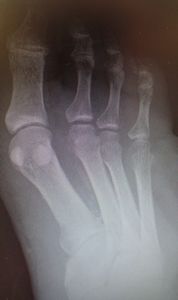

2016年2月中旬から発熱が続き,近くの〇〇病院内科に通院していたが,右第5趾の色が黒くなり,2月29日に△△院に救急搬送された。ここで初めて糖尿病指摘(血糖450,HbA1c 14)の指摘を受けた(内服薬で血糖コントロール中)。

入院後,同院整形外科で直ちに第5趾切断術。その後,2度追加手術(デブリードマンらしい)。3月7日よりVAC療法。現在はプロスタンディン軟膏とガーゼで治療。治癒しないため,当科紹介となった。